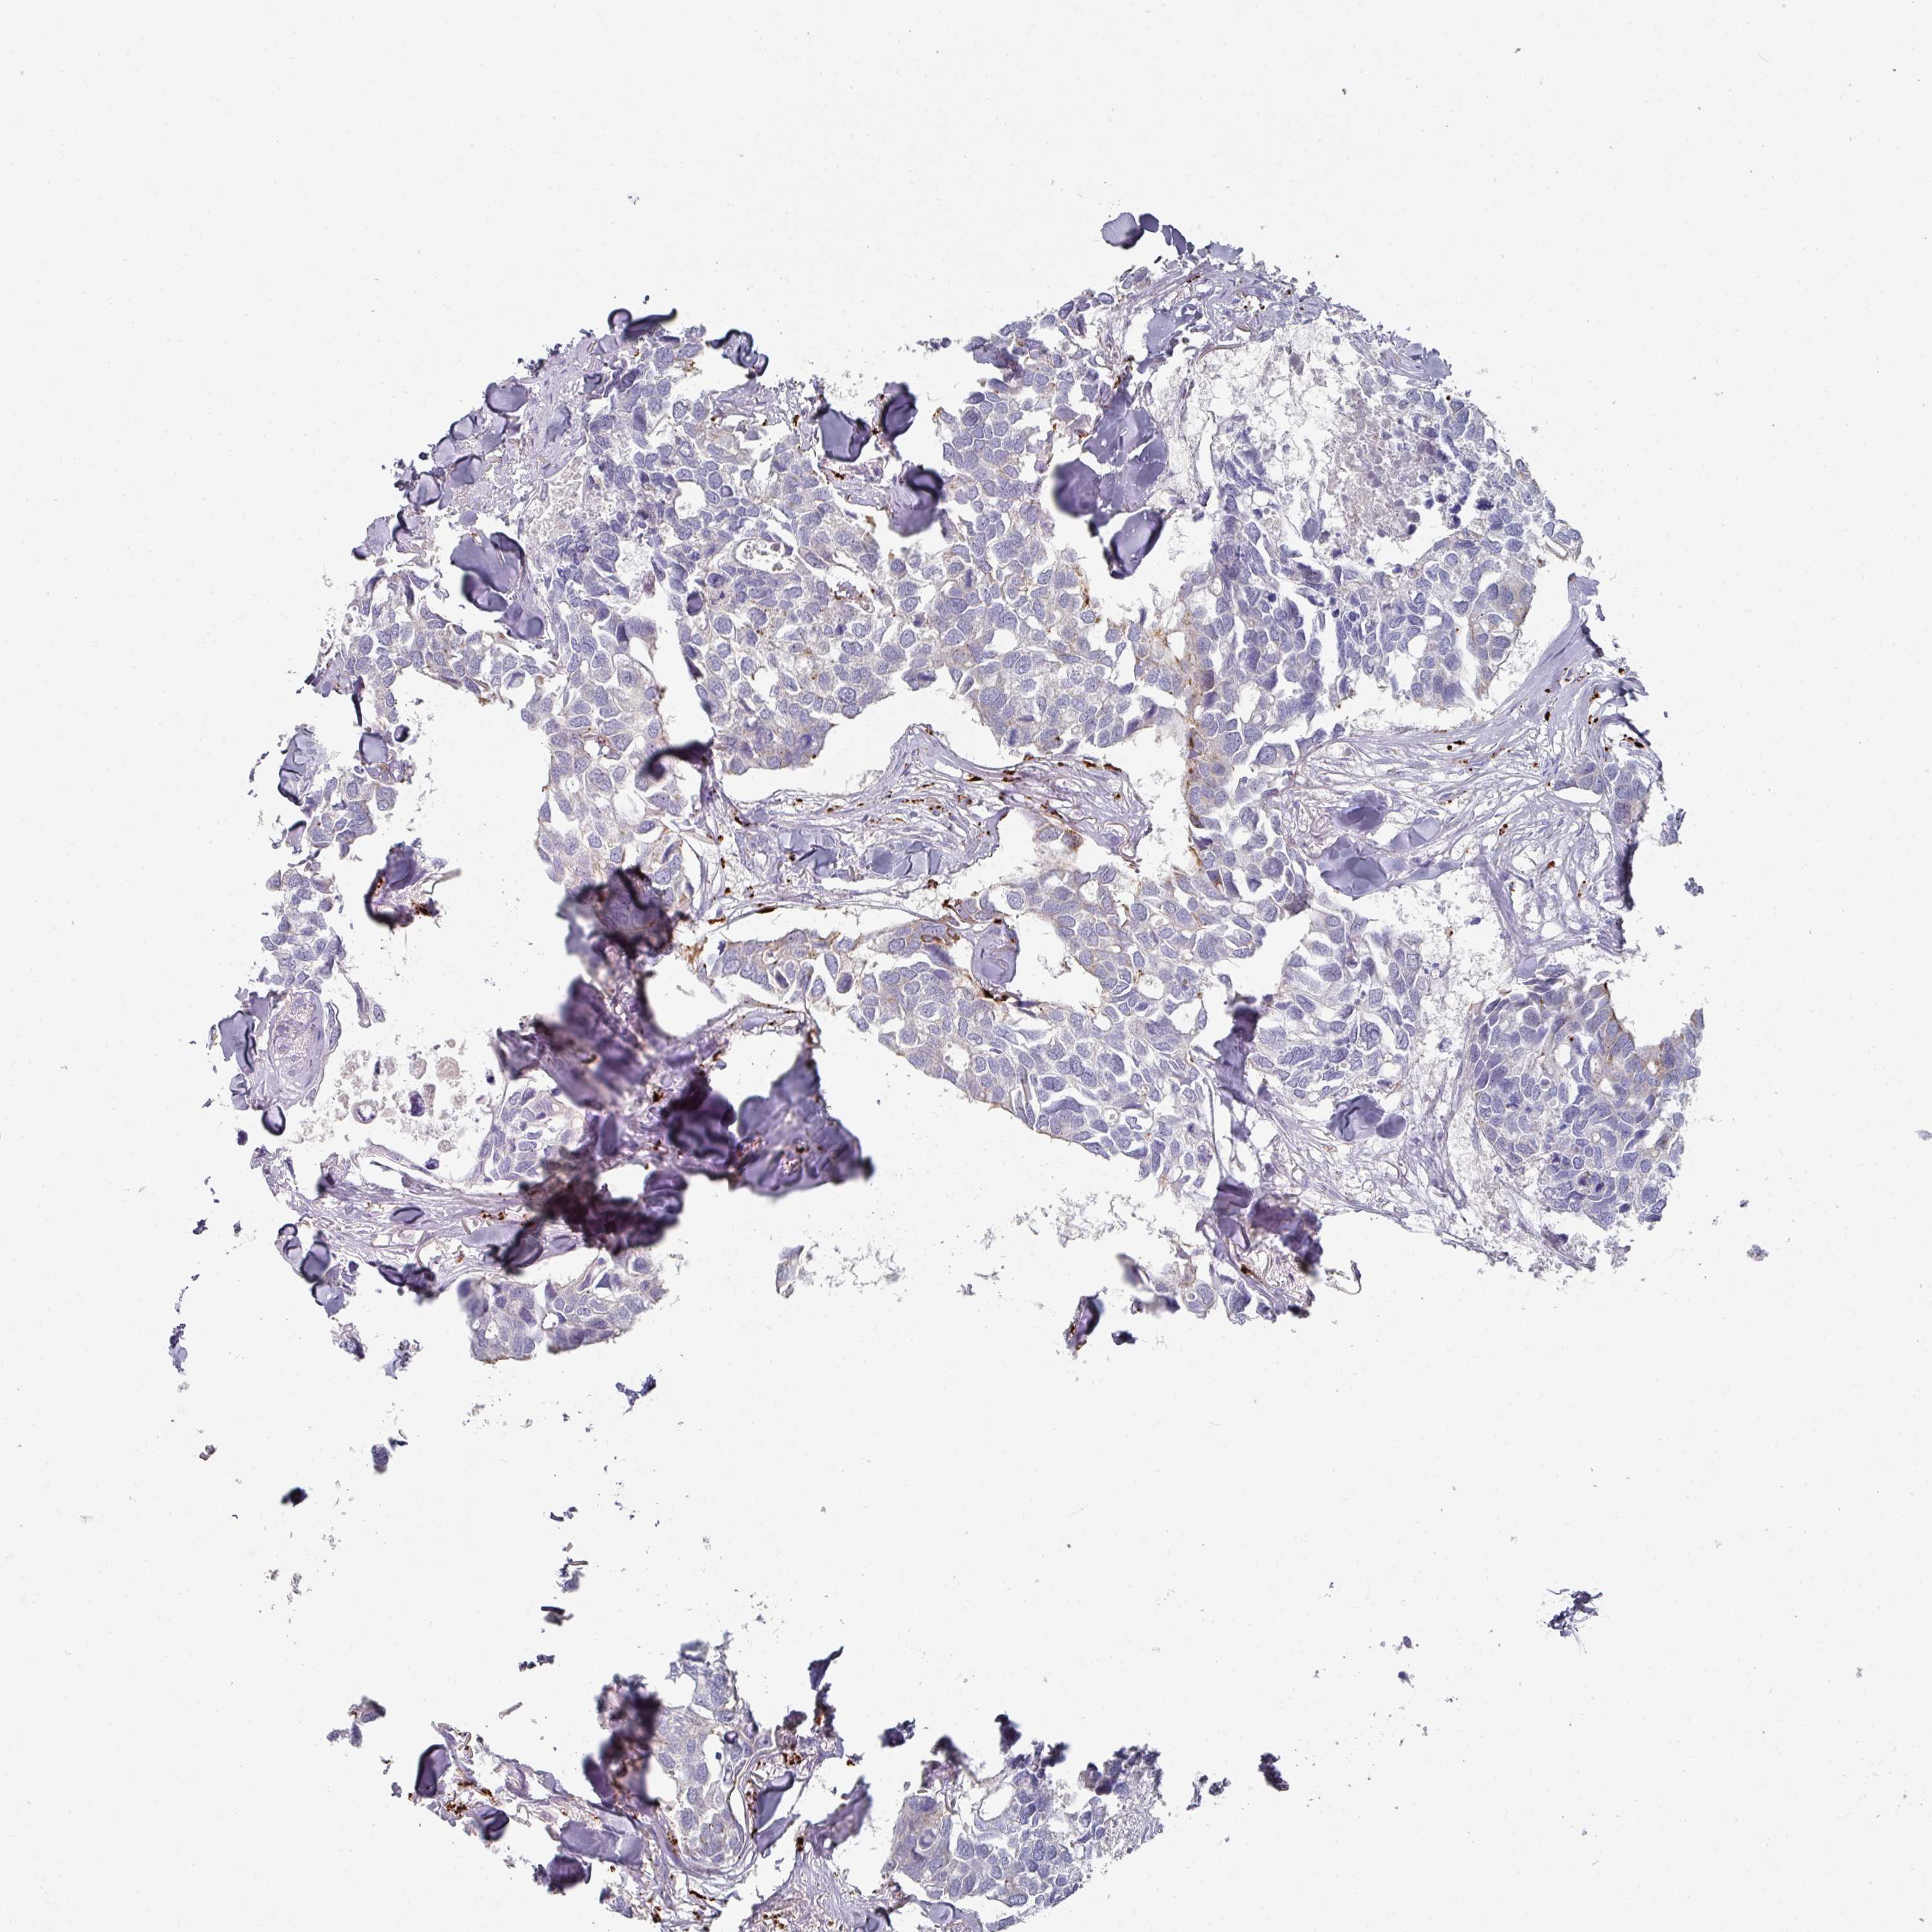

CANCER BREAST CANCER Show tissue menu

BRCA TCGA BRCA VALIDATION PROTEIN EXPRESSION